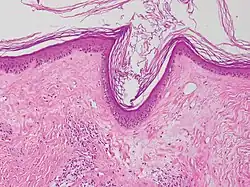

Typische histopathologische Merkmale des Lichen sclerosus sind eine Atrophie der Epidermis mit vakuolärer Degeneration der Keratinozyten (hornbildende Zellen der Epidermis) in der basalen Zellschicht und Sklerose der korrespondierenden Dermis. Der Sklerosezone grenzt zur Tiefe ein zumeist bandartig angeordnetes Entzündungsinfiltrat aus Lymphozyten an. Weitere mögliche Veränderungen sind eine unregelmäßige Akanthose (Verbreiterung des Stratum spinosum der Epidermis) und Hyperkeratose der Epidermis (hypertrophische Form), auf behaarter Haut mit Hyperkeratosen der Haarfollikel.[19]

In extragenitalen Läsionen fehlt häufig die Atrophie und das Entzündungsinfiltrat kann eosinophile Granulozyten enthalten. In der Dermis zeigen sich hier häufiger aufgeweitete kleine Blutgefäße.[20][21] Klinisch bullöse Läsionen gehen mit einem dermalen Ödem bis hin zur subepidermalen Blasenbildung einher.

Lichen sclerosus (atrophische Form) -

Lichen sclerosus (hypertrophische Form) -

Lichen sclerosus mit follikulärer Hyperkeratose